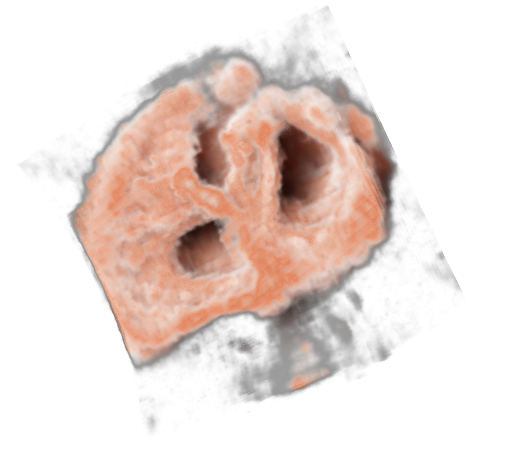

To increase robustness of the ultrasound segmentation, the various approaches are usually tailored for specific anatomies. Carneiro et al. have developed an automatic technique for segmenting the brain of a fetus carneiro08 . By first detecting the cerebellum, the system can narrow down the search for other features. On the other hand, segmentation is an extremely critical procedure which may obscure diagnostically relevant aspects of the anatomy under examination. Consequently, fully automatic segmentation techniques have not been implemented in clinical systems so far, with the exception of a method for follicle volumetry deutch09 , as shown in figure 3.

Feature extraction can be computationally costly. In-vivo 3D ultrasound examination cannot always afford the extra time necessary to extract the interesting structures. Therefore clipping is commonly used tool in live visualization of 3D ultrasound. Interactively removing regions which are not interesting, the user gets a clear view of the features normally occluded. Sakas et al. developed a clipping tool in their ultrasound visualization system sakas95 which is nowadays a standard feature in commercial 3D ultrasound systems. The user can in-vivo segment the dataset using three approaches. Drawing on one of the three axially-aligned slices, selecting everything along the current axis and within the sketch. Another tool is based on sketching directly on the 3D rendered scene. Each voxel is the projected onto the screen and removed if it lies within the marked area. The third clipping tool is based on the distance from a single mouse-click on the view-plane. A hemispherical wave front is propagated from the seed-point and stops when the voxels reach user-specified threshold. Figure 4 show an example of clipping implemented in the GE Voluson machines magicut99 .